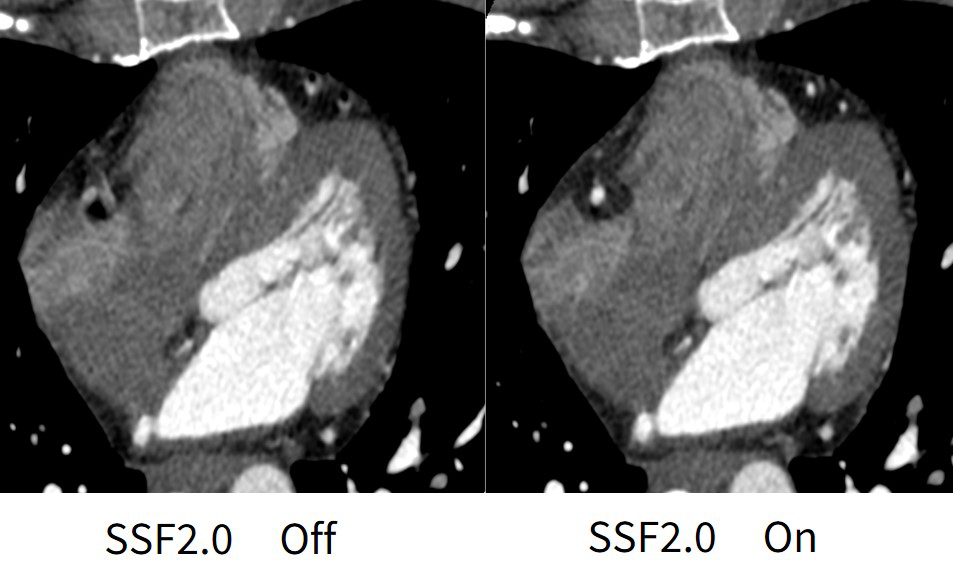

従来のSSFはターゲット心位相の前後の心位相データから冠動脈に対して3次元的動態アルゴリズムを用いて冠動脈のみモーションアーチファクト低減しているが、SSF2.0では従来のSSF同様に3つの心位相から解析して、冠動脈のみではなく、大動脈弁、僧帽弁、心筋など心臓全体に対してモーションアーチファクトを低減している。SSFはSegment再構成にのみ対応しており、高心拍症例ではSSFの他にMulti sector再構成にて冠動脈解析を必要とする場合もあった。

SSF2.0においてもSegment再構成のみの対応となるが、図4の症例はHR70bpmでも左のSSF2.0 OFFの画像ではRCAはモーションアーチファクトにより評価困難であるのに対して、右画像のSSF2.0 ONでは75%再構成でRCAのモーションアーチファクトが大きく低減しており、評価可能であることがわかる。このようにSSF2.0ではモーションアーチファクトを大きく低減した画像を得られる事から日々の業務において最適心位相検索における時間が大幅に短縮でき、安定した画像により解析や技師レポート作成まで効率よく業務を行えている。

図4. HR:70bpm, 75%再構成